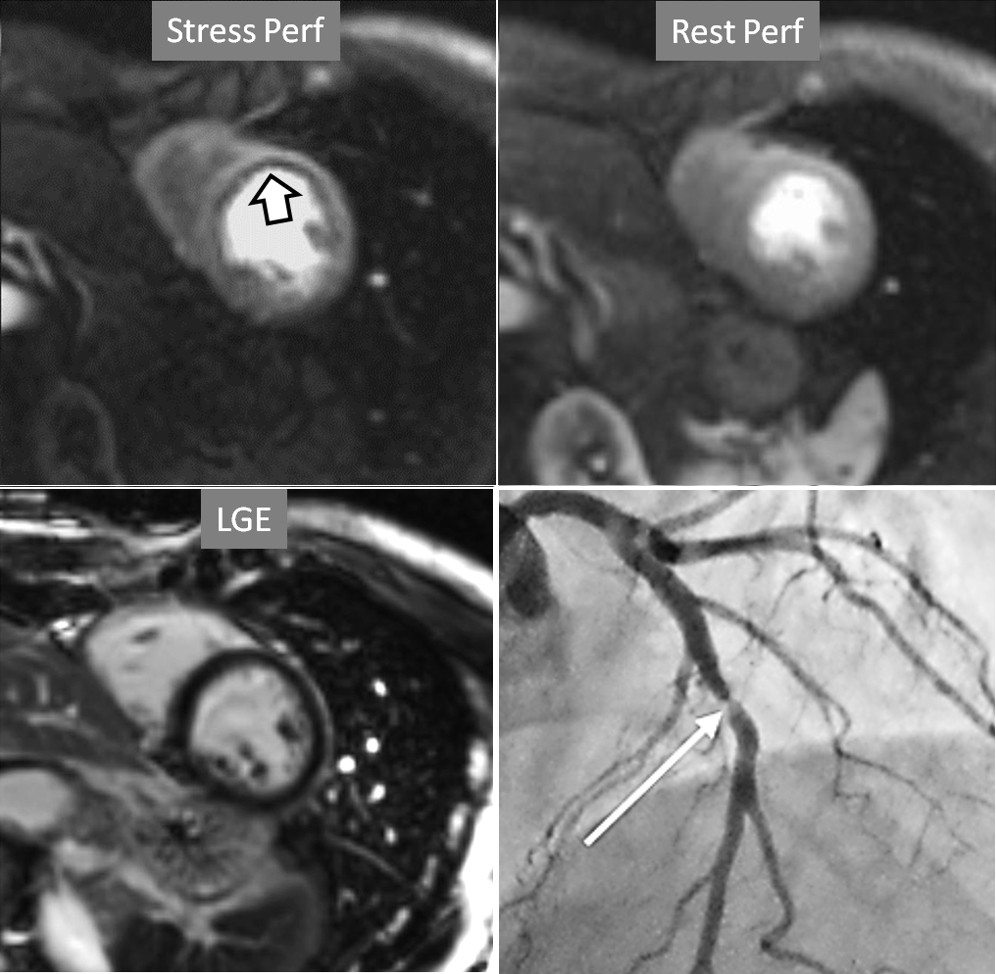

The most immediate and commonest method of analysis is the visual detection of a distinctive deficient increase in signal intensity of a region of the left ventricular myocardium during the first passage of a CA bolus under vasodilatory conditions lasting for at least 3 consecutive frames of the sequence. This perfusion defect should not be present at rest and should not correspond to an area of previous MI. The detection of such a defect is assumed to be due to a reduction in CFR of this territory which, when attributed to a particular coronary artery [39], allows for the conclusion of the presence of a significant epicardial stenosis in the vessel (Fig. 6).

Fig. 6.Single-vessel perfusion defect. Extensive subendocardial perfusion defect at the antero-septal region (arrow, on the upper left panel) not present at rest, in a region without LGE (lower left panel). Angiography proves this defect to be due to a tight stenosis of the LAD coronary artery (arrow, on the lower right panel).

Criteria for an appropriate interpretation of dark, unenhanced regional myocardial signals as due to perfusion defects have been issued by scientific societies [40]. According to these recommendations, it is accepted that a true defect (1) appears when contrast arrives at the left ventricular myocardium, (2) persists for several cardiac cycles, (3) is not restricted to a thin linear contour, (4) it is more prominent at the subendocardial level, extending variably through the whole thickness of the myocardium, (5) it is not present at rest, and (6) corresponds to a distribution territory of a coronary artery.